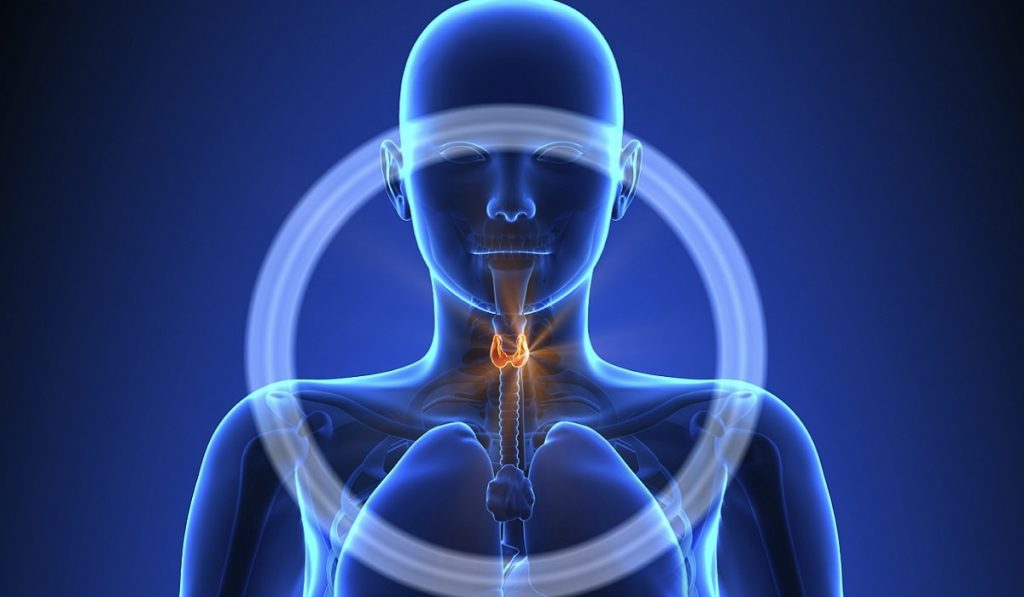

Tiroid bezi insan vücudunda çok önemli bir yere sahiptir. Tiroid hormonlarının salınımını sağlayan bu bezler aynı zamanda birçok yaşamsal aktiviteyi de kontrol eder. Tiroid bezlerinin çalışması neticesinde üretilen hormonun sistemsel olarak bozulması ve dengenin yok olması ise çeşitli tiroid hastalıklarının ortaya çıkmasına sebep olmaktadır. Tiroid bezlerinin az ya da çok çalışmasına bağlı olarak hastalıklar farklı özellikler kazanır.

Daha önce sizlere tiroid bezlerinin normalden fazla çalışması ile ortaya çıkan hipertiroidi hastalığından bahsetmiştik. Bu yazımızda ise bunun tam tersi bir durum olan hipotiroidi veya hipotiroidizm konusunu anlatacağız. Hipotiroidi, tiroid bezlerinin az çalışmasına bağlı olarak ortaya çıkar. Hipertiroidizme göre daha sık rastlanmaktadır. Kadınlarda görülme sıklığı daha fazla olan hipotiroidi, 55 – 60 yaşlarında daha fazla ortaya çıkmaktadır.

Boyun bölgesinin alt tarafında bulunan tiroid bezlerinin az çalışması sonucu, T3 ve T4 hormonlarının yeteri kadar salgılanmaması ile ortaya çıkan hastalığa hipotirodi veya hipotiroidizm adı verilmektedir. Bebekler, çocuklar ve erişkinler olmak üzere her yaştan bireyde görülebilmektedir. Belirtiler ortaya çıkar çıkmaz tedaviye başlanmalıdır.